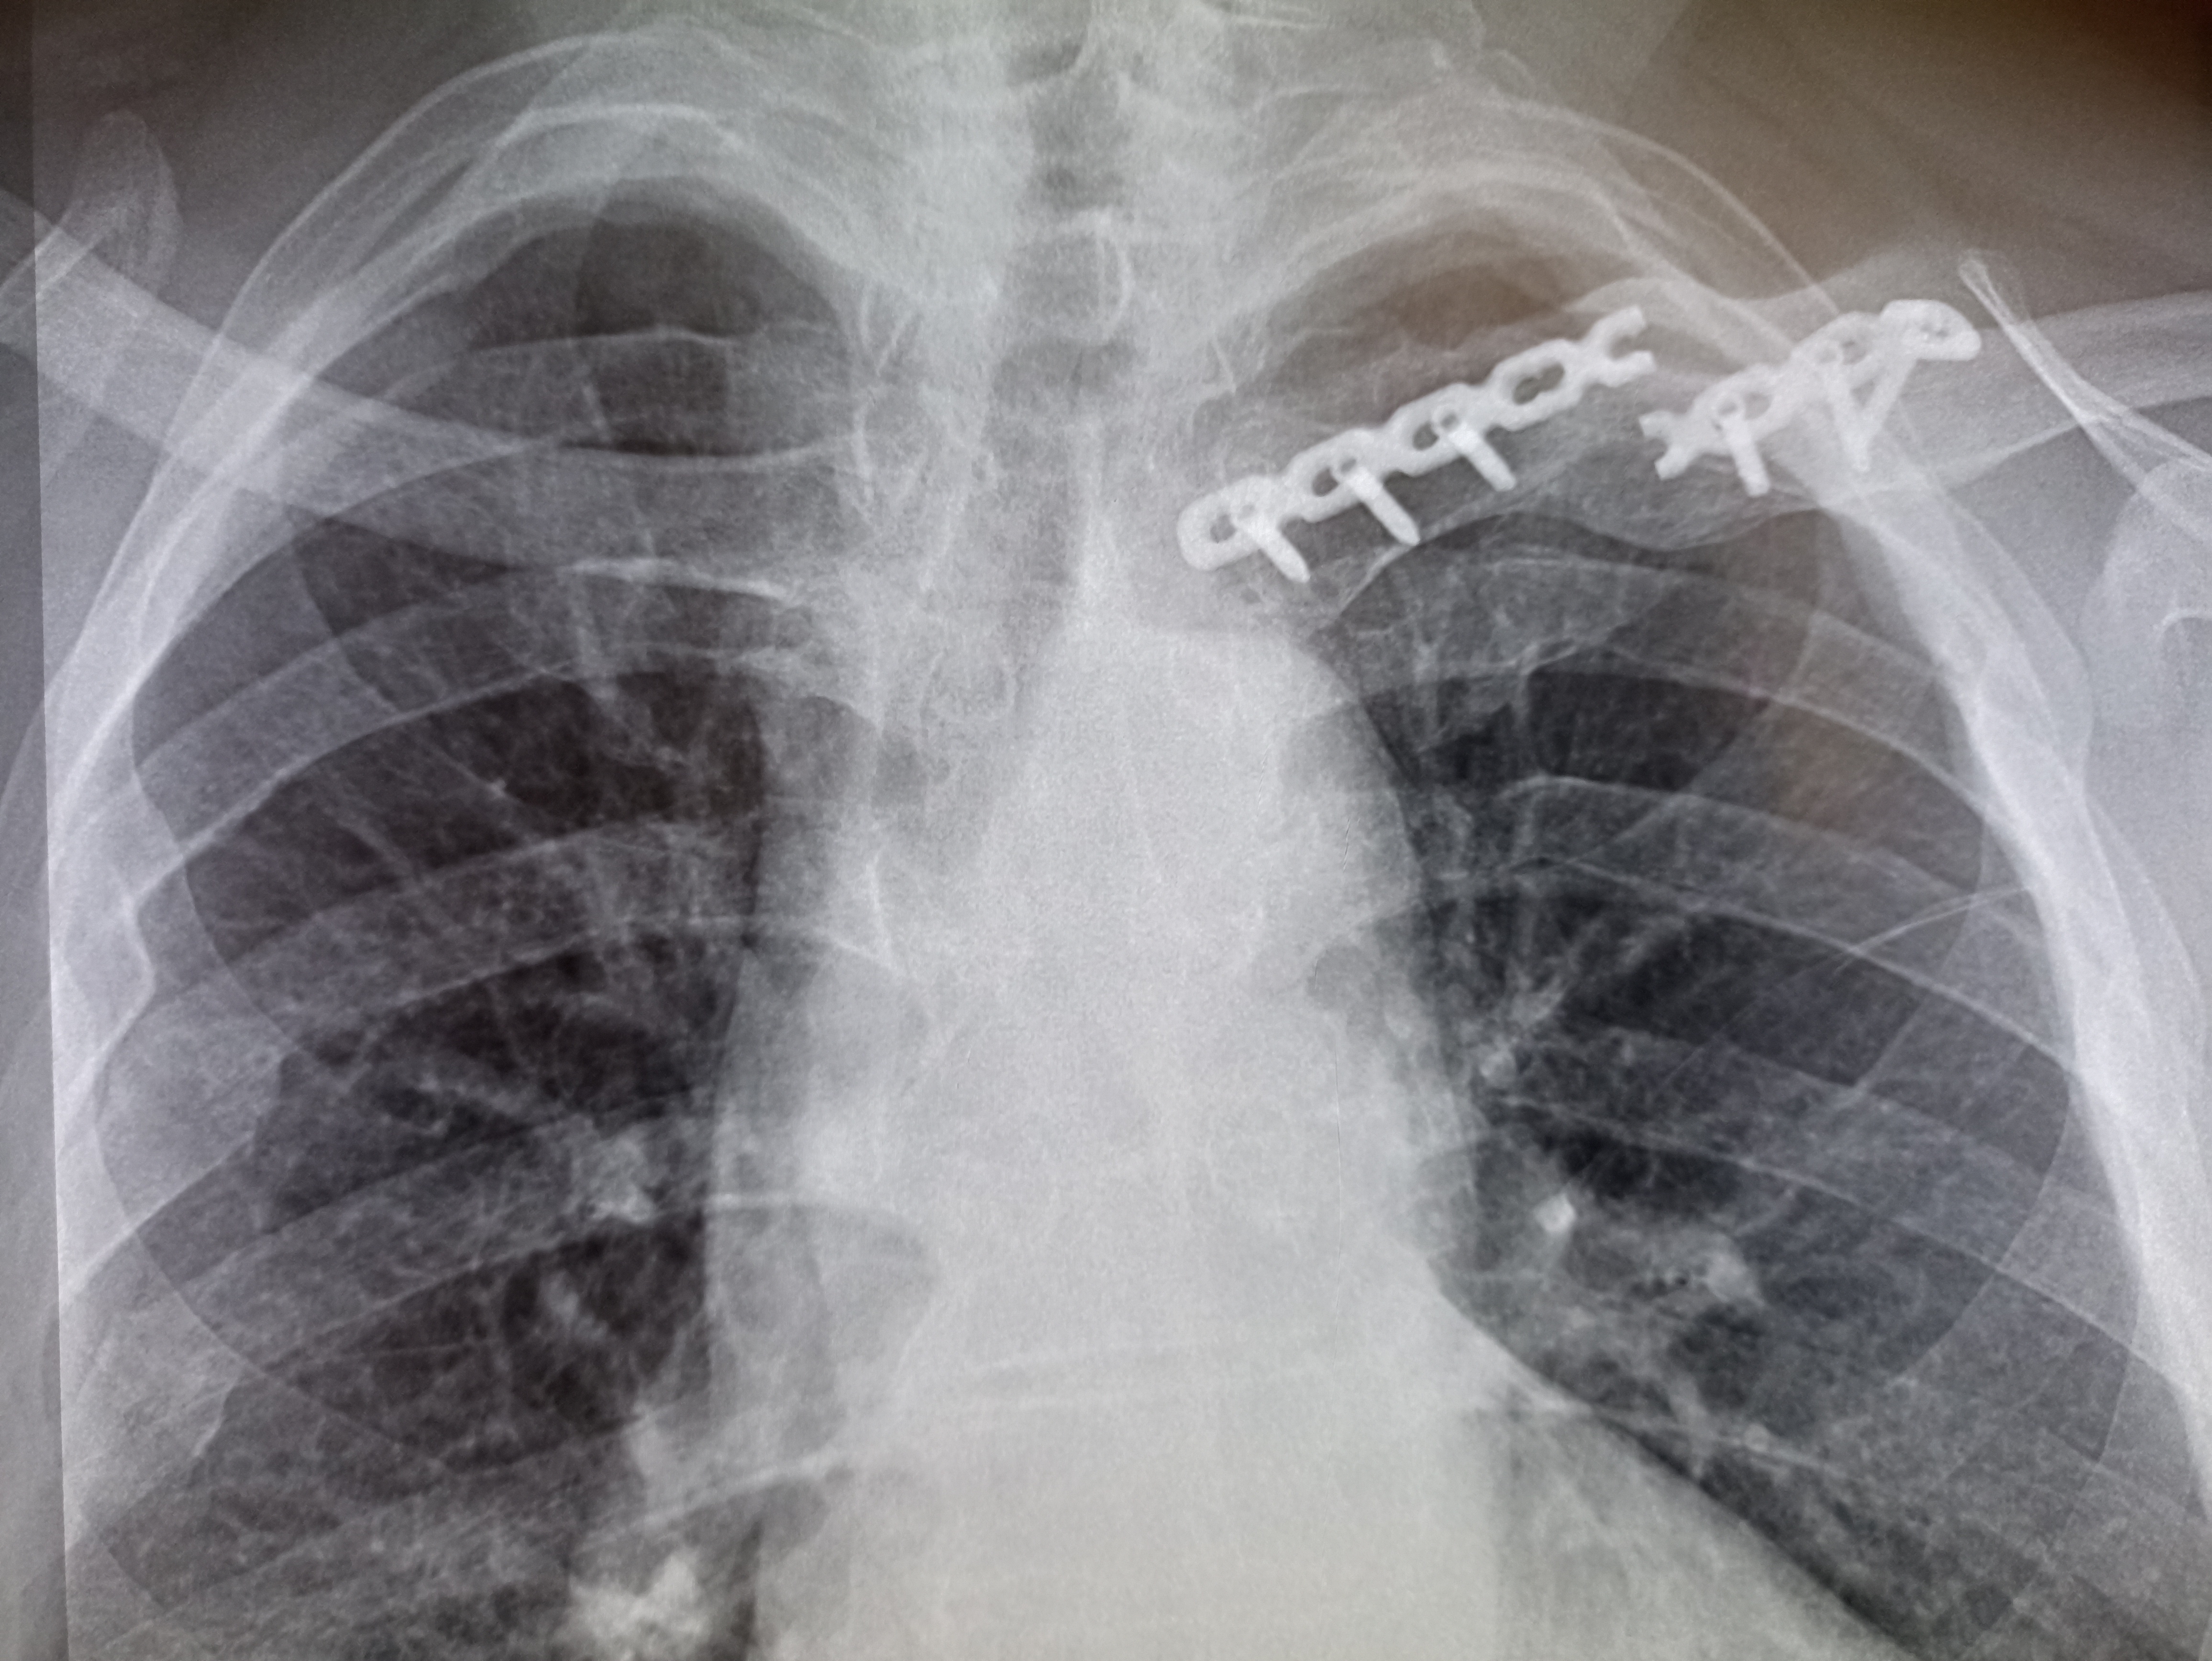

IMG20251009125406.jpg

Где пиздецома?

>>325599559

Типичный рак легких

>>325599617

Сфигаль?

>>325599891

тут явно что то справа. Там скобы после операции, туда отклоняется трахея (?) и средостение. Может часть легкого удалили?

тут затемнения двухсторонние. Почему бы не пневмония?

вообще, как клинический диагноз. я бы предположил тубик, тут и затемнения есть и в корнях кругленькие л/у? и какая то диссеминация справа.

>>325598833

тут справа что- то удаляли, все средостение смещено.